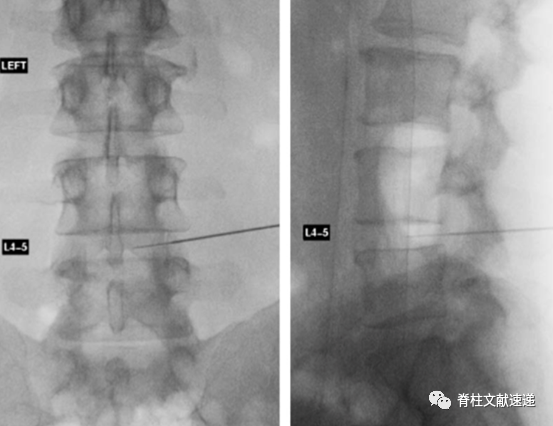

骶1神经根通过腰5/骶1椎间孔阻滞时会可能同时阻滞腰5神经根,不能精确鉴别,故阻滞骶1神经根可通过骶1孔来实现。具体操作如下。

2.1.  俯卧位,常规消毒,定位,正位时调整C臂机,与L5/S1椎间隙平行,黑圈所示为骶1孔,后孔易与较大的前孔混淆(上图A)

2.2.  先将穿刺针扎中骶1孔远端的骶骨(上图B),再逐渐滑行调整至骶孔(上图C)。

2.3.  侧位透视,针尖不应该位于骶管腹侧,理想的位置是紧贴S1椎弓根尾下缘,位于椎板下约5mm(上图D)。

2.4.  穿刺位置良好后,抽吸测试,若无血液和脑脊液,可行造影剂观察(上图E、),再行局麻药物注入。